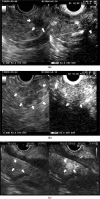

Accumulated evidence has revealed that endoscopic ultrasonography (EUS) has had a great impact on the clinical evaluation of pancreatic cancers. EUS can provide high-resolution images of the pancreas with a quality regarded as far surpassing that achieved on transabdominal ultrasound (US), computed tomography (CT), or magnetic resonance imaging (MRI). EUS is particularly useful for the detection of small pancreatic lesions, while EUS and its related techniques such as contrast-enhanced EUS (CE-EUS), EUS elastography, and EUS-guided fine needle aspiration (EUS-FNA) are also useful in the differential diagnosis of solid or cystic pancreatic lesions and the staging (T-staging, N-staging, and M-staging) of pancreatic cancers. In the diagnosis of pancreatic lesions, CE-EUS and EUS elastography play a complementary role to conventional EUS. When sampling is performed using EUS-FNA, CE-EUS and EUS elastography provide information on the target lesions. Thus, conventional EUS, CE-EUS, EUS elastography, and EUS-FNA are essential in the clinical investigation of pancreatic cancer.